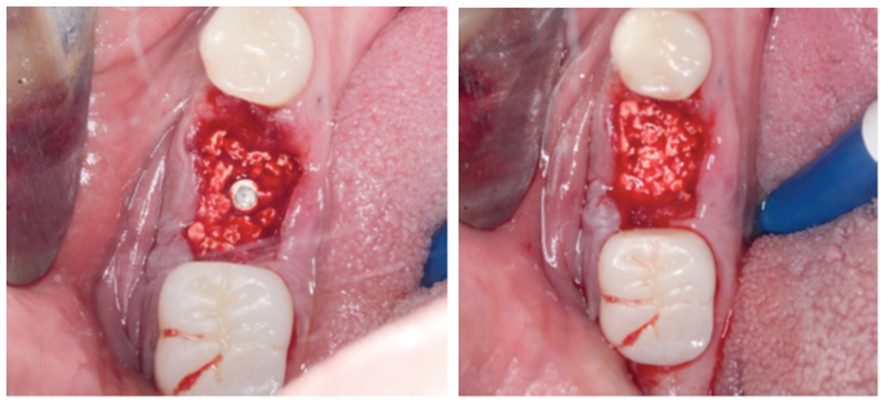

Para a regeneração óssea guiada, o substituto ósseo natural composto por hidroxiapatita bovina e colágeno do tipo I (Extra Graft XG-13) foi introduzido ao redor do implante para preenchimento do GAP (Figura 7). Depois, uma barreira regenerativa não absorvível (Cytoplast) foi recortada, adaptada e colocada, seguida por uma membrana biológica bovina (Figuras 8 e 9). O procedimento cirúrgico foi finalizado com a realização da sutura com fio de nylon 5.0. Para verificar o posicionamento do implante dentário, uma radiografia periapical foi realizada imediatamente à cirurgia (Figura 10).